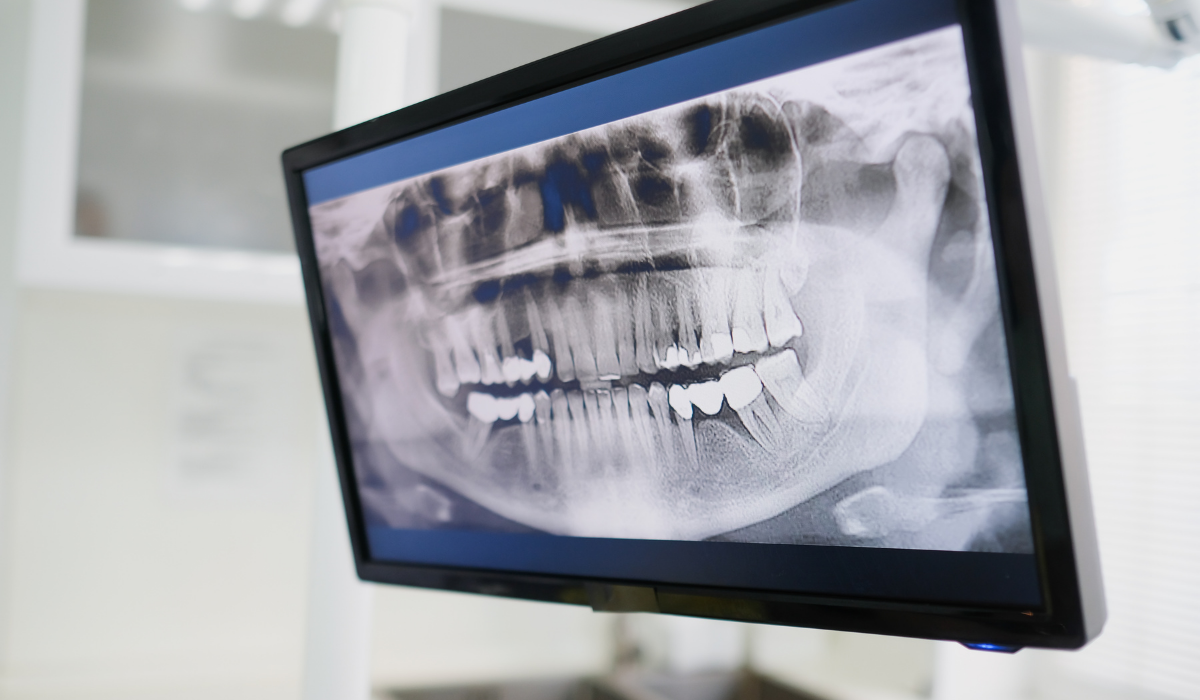

연말정산, 임플란트 시술비도 공제받을 수 있다? 알고 보면 쏠쏠한 의료비 공제 혜택!

많은 분들이 임플란트 시술을 받지만, 연말정산 시 의료비 공제 혜택을 놓치는 경우가 많습니다. 임플란트 시술은 고가의 치료인 만큼, 공제 혜택을 꼼꼼히 챙겨 세금 부담을 줄이는 것이 현명합니다. 오늘은 연말정산 시 임플란트 시술비 공제에 대해 자세히 알아보고, 최대한 혜택을 받을 수 있는 방법을 함께 살펴보겠습니다.